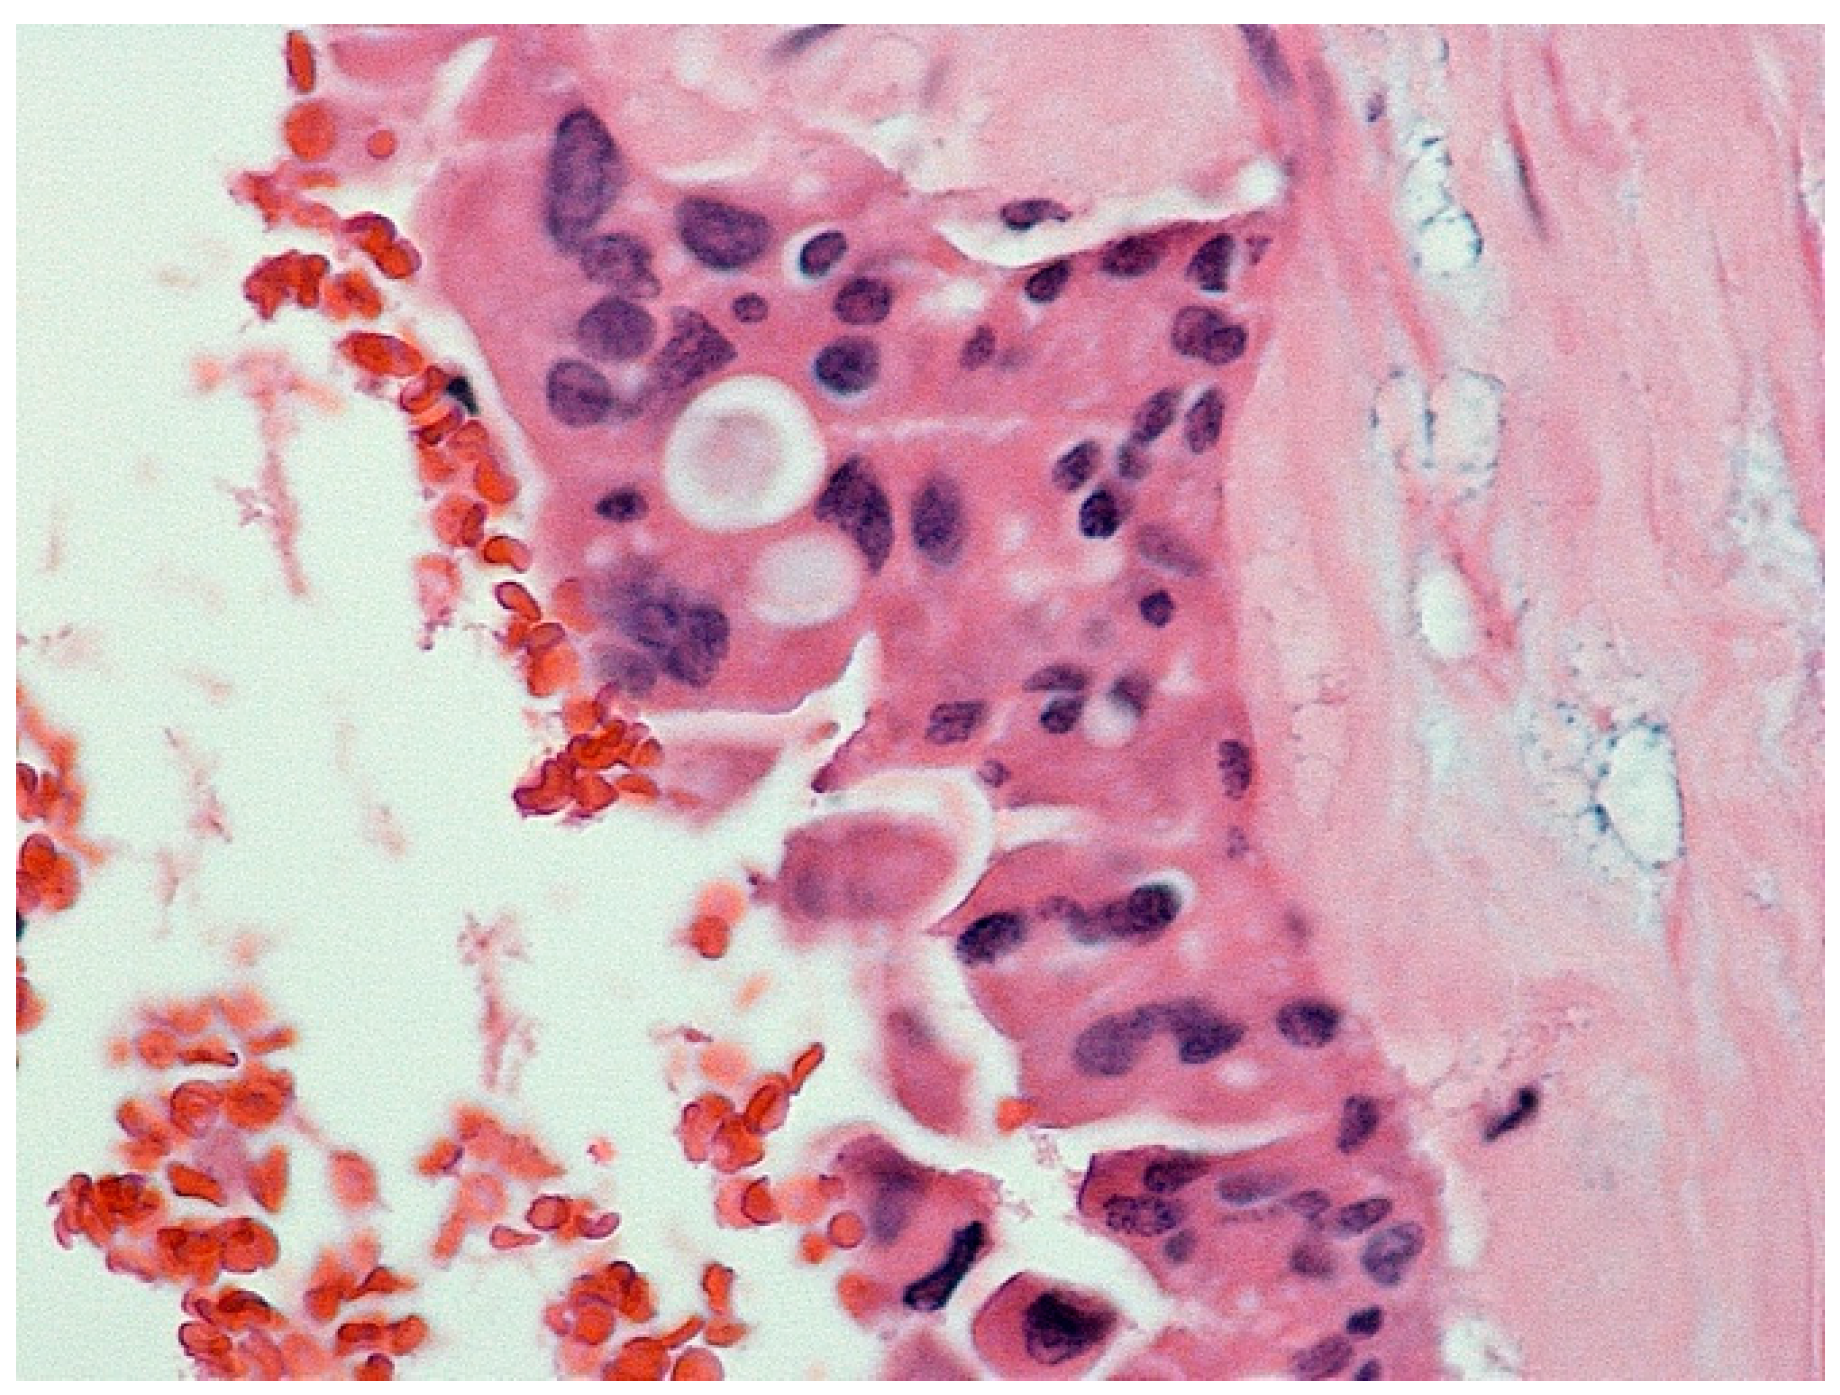

| Histopathological Findings | IPNB with foci of adenocarcinoma, oncocytic appearance, varying degrees of dysplasia, mucus within cyst | Adenocarcinoma with papillary clear cell and mucinous appearance, gland ectasis, cystic or pseudocystic aspects |